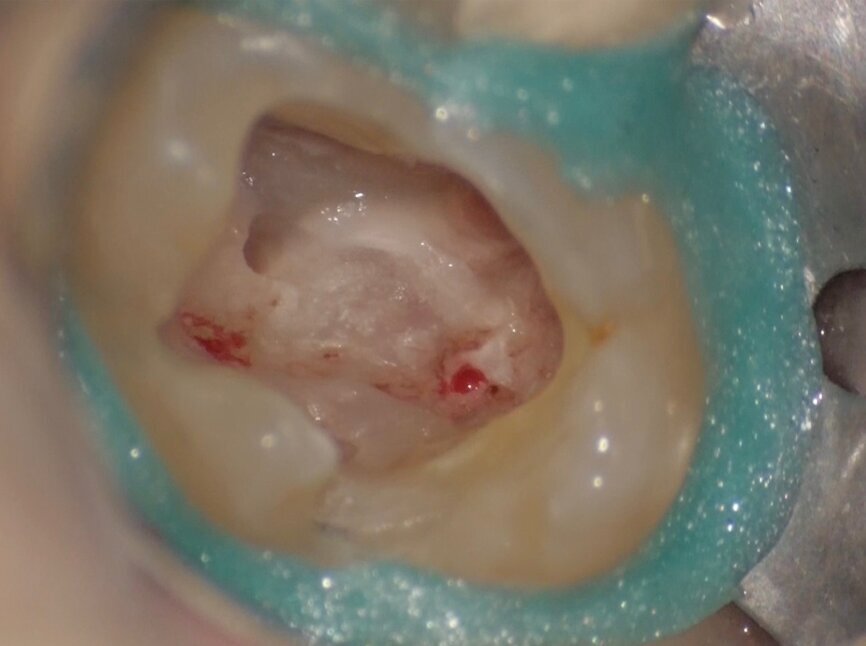

Comparing the two teeth shown in Figures 10 to 22 demonstrates just how important it is to analyse all the slices of the CBCT study correctly. We can see that, in the maxillary molar, the lesion penetrates into the pulp chamber, starting from the root’s distal surface, but remains within the coronal third of the tooth, without significantly affecting the integrity of the pulp chamber floor (Figs. 10–15). The clinical images illustrate the operative treatment phases, from resorption debridement through to repair using bioceramic cement (Figs. 16–19). The final radiographic images confirm the validity of the conservative and endodontic treatment of the tooth. The situation is completely different for the mandibular molar, where the evaluation of the CBCT scan clearly reveals the extent of the resorption, which invades the pulp chamber floor until the furcation, a situation that cannot be determined from observing the preoperative radiograph alone (Figs. 20–22).